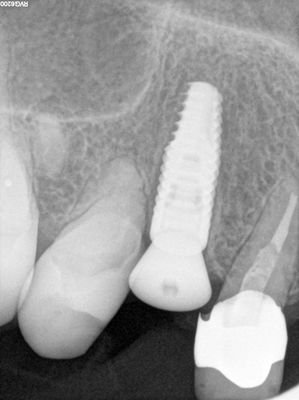

NSankhyan - immediate 13, impls 1121 and 25 with grafting

13 exo, loss of labial plate, implant placed buccal region grafted with sticky bone and collagen membrane soaked in prf fluid. 11/21 limited Labial-palatal width of bone, ridge split to 5mm, osteotomies prepared to about 2mm, remainder with densah drills, implants placed with ample bone, buccal grafted with same sticky bone. densah drills used for apical portion of 25 implant, soft bone, implant placed